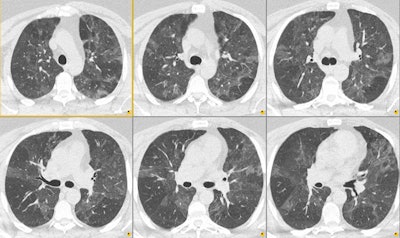

Mosaic attenuation due to air trapping:

Inspiratory CT demonstrated mosaiform attenuation to the lung parenchyma. On expiration, areas of decreased attenuation persisted which confirmed air trapping as the etiology of the mosaiform attenuation in this patient.

Inspiration:

Expiration:.